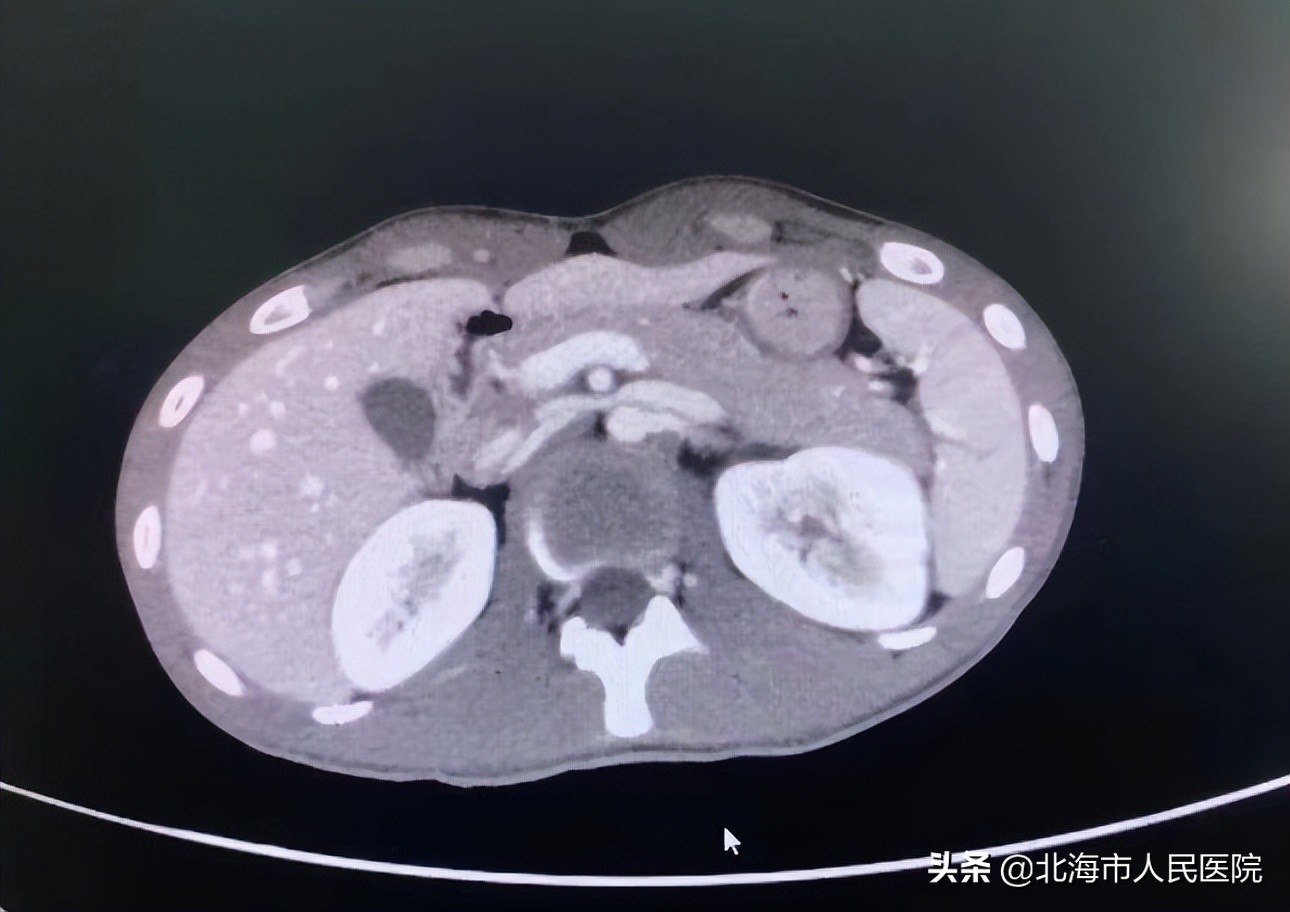

患者在当地医院做了B超、拍了片后,并未发现什么,但之后几天他一直不停排出血尿,于是为了进一步治疗来到市人民医院就诊。收入院后,经进一步CT检查,发现患者排血尿的原因是摔伤时导致“创伤性脾破裂和肾挫伤”。

肿瘤二区副主任、副主任医师张成文介绍,该患者因外伤导致脾破裂、肾挫伤,因此频繁尿血,必须尽快为其手术止血,根据患者病情选择合适的栓塞剂,一般不建议长效栓塞剂。